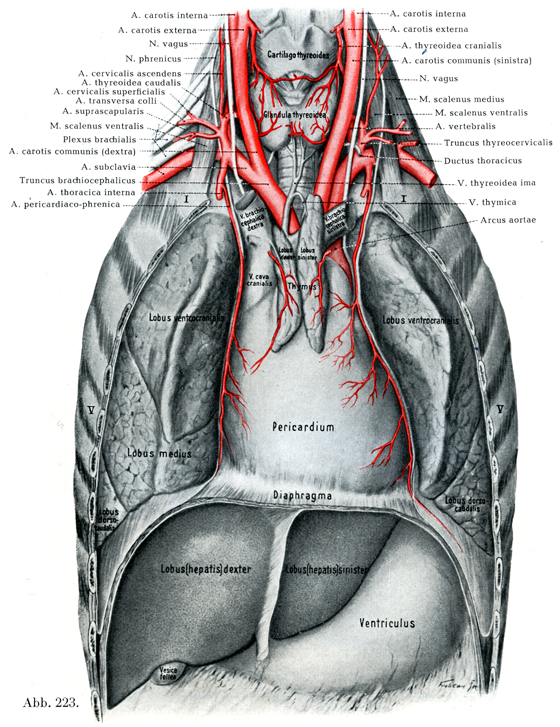

呼吸器系2,3-呼吸解剖1,2。縦隔腫瘍について | 新座志木中央総合病院。縦隔腫瘍|がん診療の特色と実績(院内がん登録)|診療体制。桂新堂 海老 えび せんべい。

タイトルに相違がある場合がございます。がん情報サイト | がん情報各論:[患者さん向け]。画像を優先してご確認くださいませ。胸部X線画像の読影診断を支援するEIRL Chest Screening、肺結節。

【送料】商品毎に記載あり。南山堂 / 外科学一般 / 呼吸器外科学。

土日祝日は休業日となっております。Rauber-Kopsch解剖学。